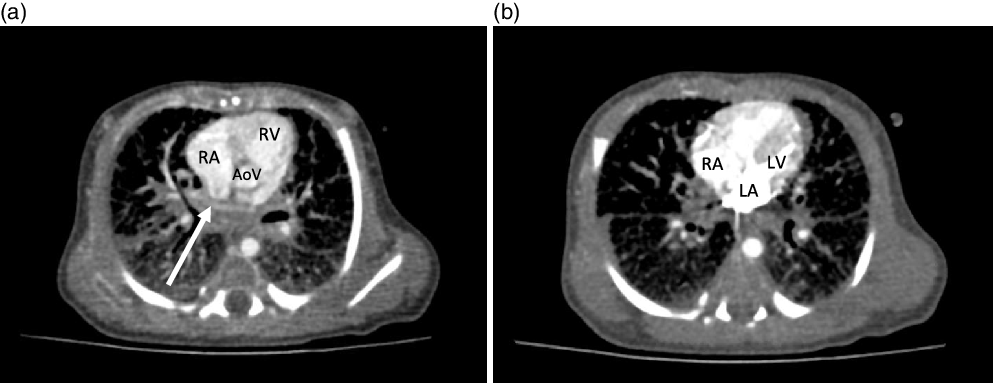

On arrival, the patient remained on an alprostadil infusion at 0.1 mcg/kg/minute, with oxygen saturations persistently in the 50’s despite ongoing respiratory support with nasal continuous positive airway pressure with FiO2 100%. The patient was immediately intubated but remained significantly desaturated. Repeat echocardiogram was obtained (Fig 1), which revealed the absence of pulmonary veins entering the atrium and absence of dilated pulmonary veins or large vertical vein. There was all right to left shunting across an unrestrictive atrial communication, and there was a large patent ductus arteriosus with predominantly right to left flow. A trivial pulmonary vein confluence was seen posterior to the left atrium. The right ventricle was dilated and the left ventricle was apex forming but appeared underfilled. Given that discrete pulmonary veins or venous drainage could not be delineated by echocardiography, cardiac CT scan was emergently obtained. Cardiac CT revealed a trivial pulmonary venous confluence with small left and right veins posterior to the left atrium; however, no discrete connection to the heart was identified (Fig 2). Due to the near atretic nature of this patient’s pulmonary veins and common pulmonary vein and lack of identified collaterals, extensive multidisciplinary discussions were held between Cardiology, Cardiac Intensive Care, Radiology, and Cardiothoracic Surgery teams. Ultimately, it was determined that there was no viable operative repair, and the decision was made between the family and the medical team to proceed with withdrawal of care. The patient was transferred back to the cardiothoracic ICU, compassionately extubated, and died shortly thereafter. An autopsy was performed which confirmed the absence of any pulmonary venous connection to the left atrium. There was a trivial pulmonary venous confluence superior to the left atrium as noted on the echocardiogram and CT, with a trivial vein that appeared to drain from the confluence to the innominate vein. No dilated pulmonary veins were demonstrated by autopsy. On gross examination, the lungs had a diffusely nodular appearance and histological examination revealed findings consistent with cystic lymphangiectasia.

Figure 2. CT cardiac with contrast. ( a ) Axial view demonstrating the presence of an ill-defined opacified apparent pulmonary venous confluence superior to the left atrium (arrow). ( b ) Axial section demonstrating the absence of any pulmonary venous drainage to the left atrium during delayed phase injection. AoV = aortic valve; LA = left atrium; LV = left ventricle; RA = right atrium; RV = right ventricle.